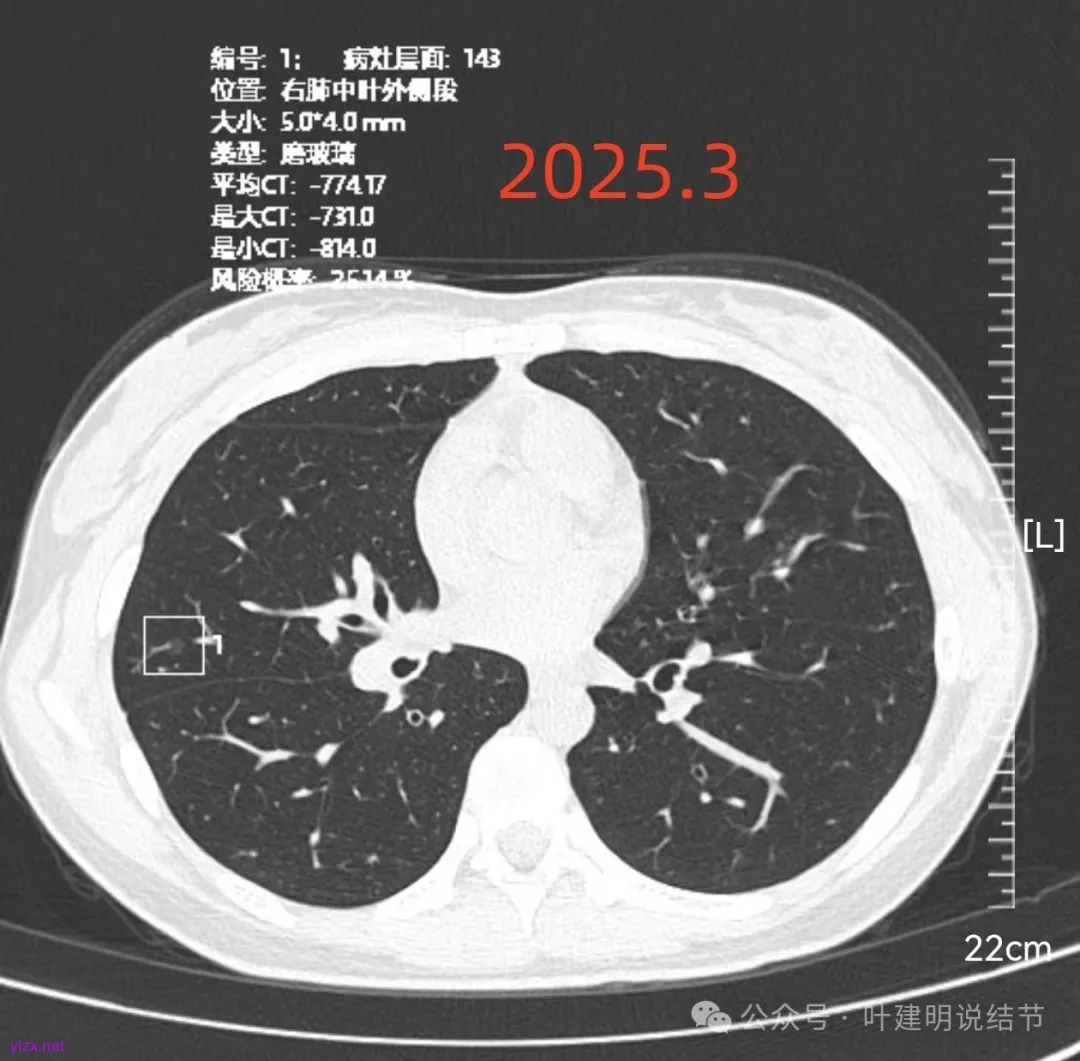

再看2025年3月的影像:

各病灶均无明显吸收好转,但显然也说不上有明显进展。所以基本上要考虑是肿瘤范畴的(包括肺泡上皮不典型增生或肺泡上皮增生)。但危险性显然不算高,至少近2年了没有什么进展,即使病灶6最厉害的也是纯磨密度伴空腔。